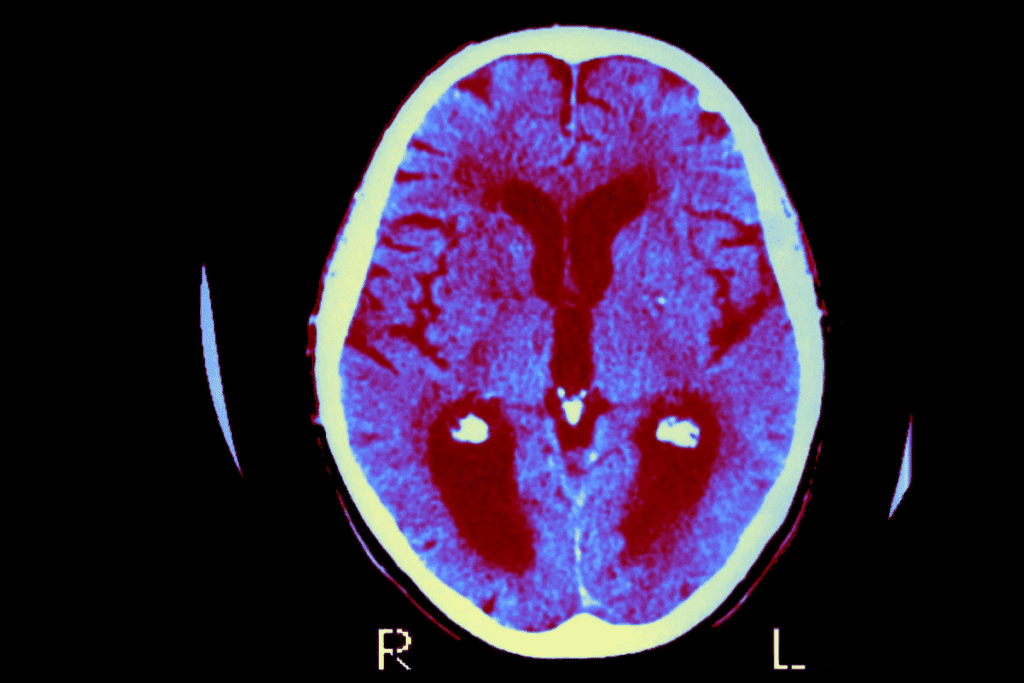

Monitoring and Detecting Recurring Tumors

Early detection of recurring brain tumors is key to better treatment outcomes. After surgery, patients need close monitoring to catch any signs of tumor return early.

Imaging Protocols After Brain Tumor Surgery

Regular imaging is vital for brain tumor patients after surgery. MRI (Magnetic Resonance Imaging) is often used because it’s very good at spotting tumors again. Doctors usually recommend MRI scans every 3-6 months at first.

The type of imaging used can depend on the tumor, its location, and the patient’s health. For example, contrast-enhanced MRI helps tell apart tumor return from surgery changes.